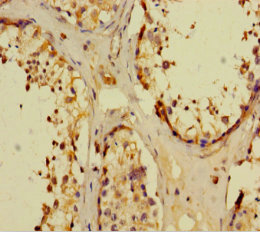

ApplicationELISA, IHC; Recommended dilution: IHC:1:20-1:200